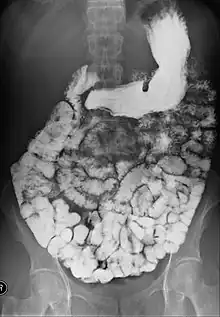

Small bowel follow-through

Indications to do this procedure are: unexplained chronic abdominal pain with weight loss, unexplained diarrhea, anemia which is caused by gastrointestinal bleeding or dependent on blood transfusion where the cause cannot be explained despite OGDS or colonoscopy investigations, partial obstruction of bowel/small bowel adhesive obstruction suspected, and unexplained malabsorption of nutrients.[13] For barium follow-through examinations, a 6-hour period of fasting is observed prior to the study.[10]

Barium is administered orally, sometimes mixed with diatrizoic acid (gastrografin) to reduce transit time in the bowel. Intravenous metoclopramide is sometimes also added to the mixture to enhance gastric emptying.[17] 600 ml of 0.5% methylcellulose can be given orally, after barium meal is given, to improve the images of small bowel follow-through by reducing the time taken for barium to pass through the small intestines, and increase the transparency of the contrast-filled small bowels.[18] Other methods to reduce transit time are to add ice cold normal saline after the administration of barium saline mixture[19] or to give a dry meal.[20]

X-ray images are then taken in a supine position at intervals of 20–30 minutes. Real-time fluoroscopy is used to assess bowel motility. The radiologist may press or palpate the abdomen during images to separate intestinal loops. The total time necessary for the test depends on the speed of bowel motility or transit time and may vary between 1 and 3 hours.[17]